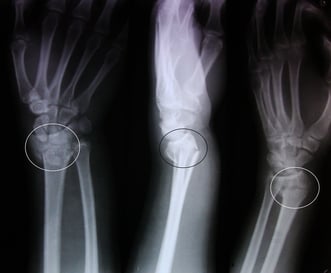

Fracturas

La fractura es una discontinuidad en los huesos, a consecuencia de golpes, fuerzas o tracciones cuyas intensidades superen la elasticidad del hueso.

El término es extensivo para todo tipo de roturas de los huesos, desde aquellas en que el hueso se destruye amplia y evidentemente, hasta aquellas lesiones muy pequeñas e incluso microscópicas.

El papel fundamental del fisioterapeuta es aliviar el dolor, evitar deformación, rigidez e impotencia funcional y corregir la movilidad articular perdida después de una fractura.